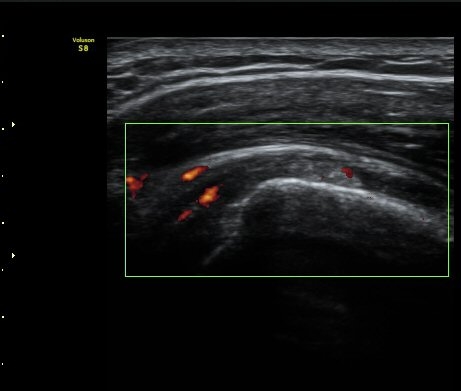

ȸÀü±Ù°³°£°Ý(rotator cuff interval) Ⱦ´Ü¸é°Ë»ç¿¡¼­ Á¡¾×³¶¸Å ¼ö¾× Àú·ù°¡ °üÂûµÈ´Ù(±×¸² 1).

±Ø»ó°Ç Á¾´Ü¸é°Ë»ç¿¡¼­ Á¤¸Æ³¶³» ¼ö¾×Àú·ù¿Í ±Ø»ó°Ç³» ¼®È¸È­À½¿µÀÌ °üÂûµÈ´Ù(±×¸² 2, 3).

ÆÄ¿öµµÇ÷¯°Ë»ç¿¡¼­ ±Ø»ó°Ç°ú Á¡¾×³¶ÁÖÀ§¿¡¼­ ¼ö¾×Àú·ù°¡ °üÂûµÈ´Ù(±×¸² 6, 7).